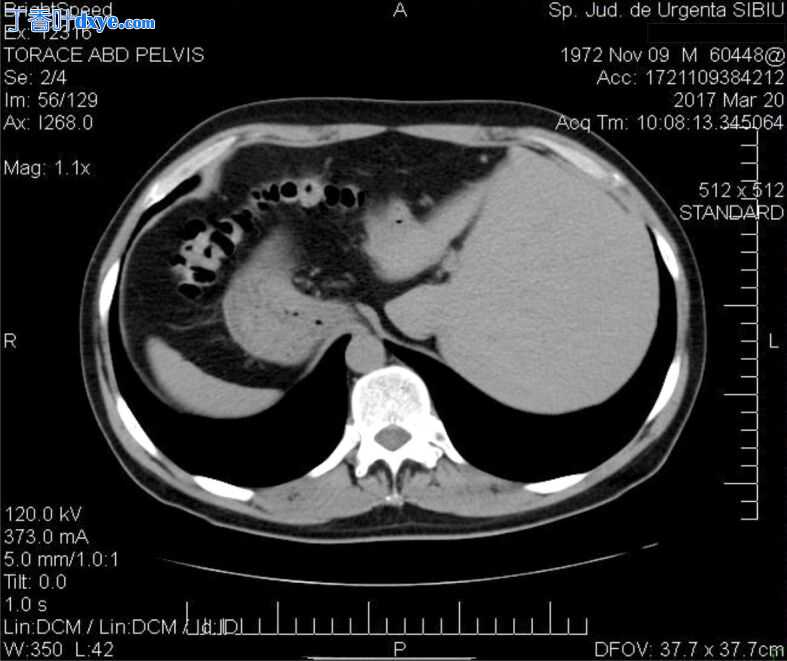

术后进展良好,恢复了肠道转运和抑制腹膜引流。 作者进行了腹部计算机断层扫描 (CT) 扫描,结果显示腹部位置反转伴右位心。

心脏评估和心脏超声(US)证实了右位心,但没有发现任何其他心脏变化((图 3、4、5)。 患者提交后三天出院。 术后 3、6 和 12 个月的随访预约未发现任何问题。

图 3

胸部 CT 扫描图像:右位心。 CT:计算机断层扫描

图 4

胃和肝脏位置异常

图 5

盲肠、阑尾发育不全